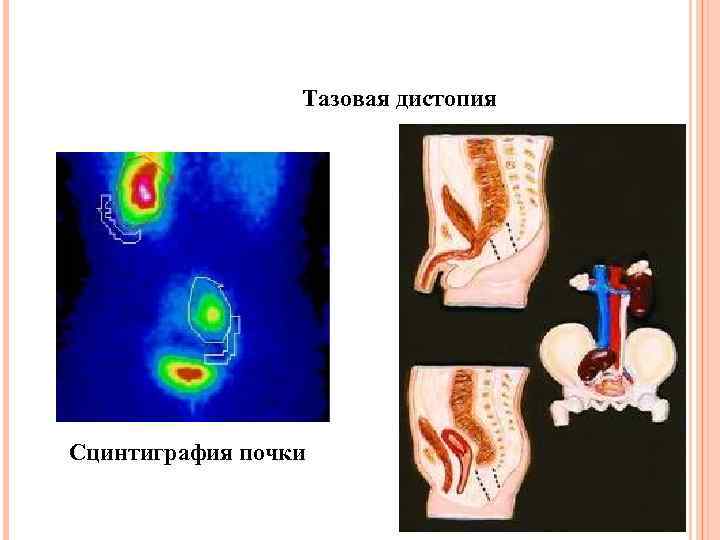

Тазовая дистопия Сцинтиграфия почки

Тазовая дистопия Сцинтиграфия почки